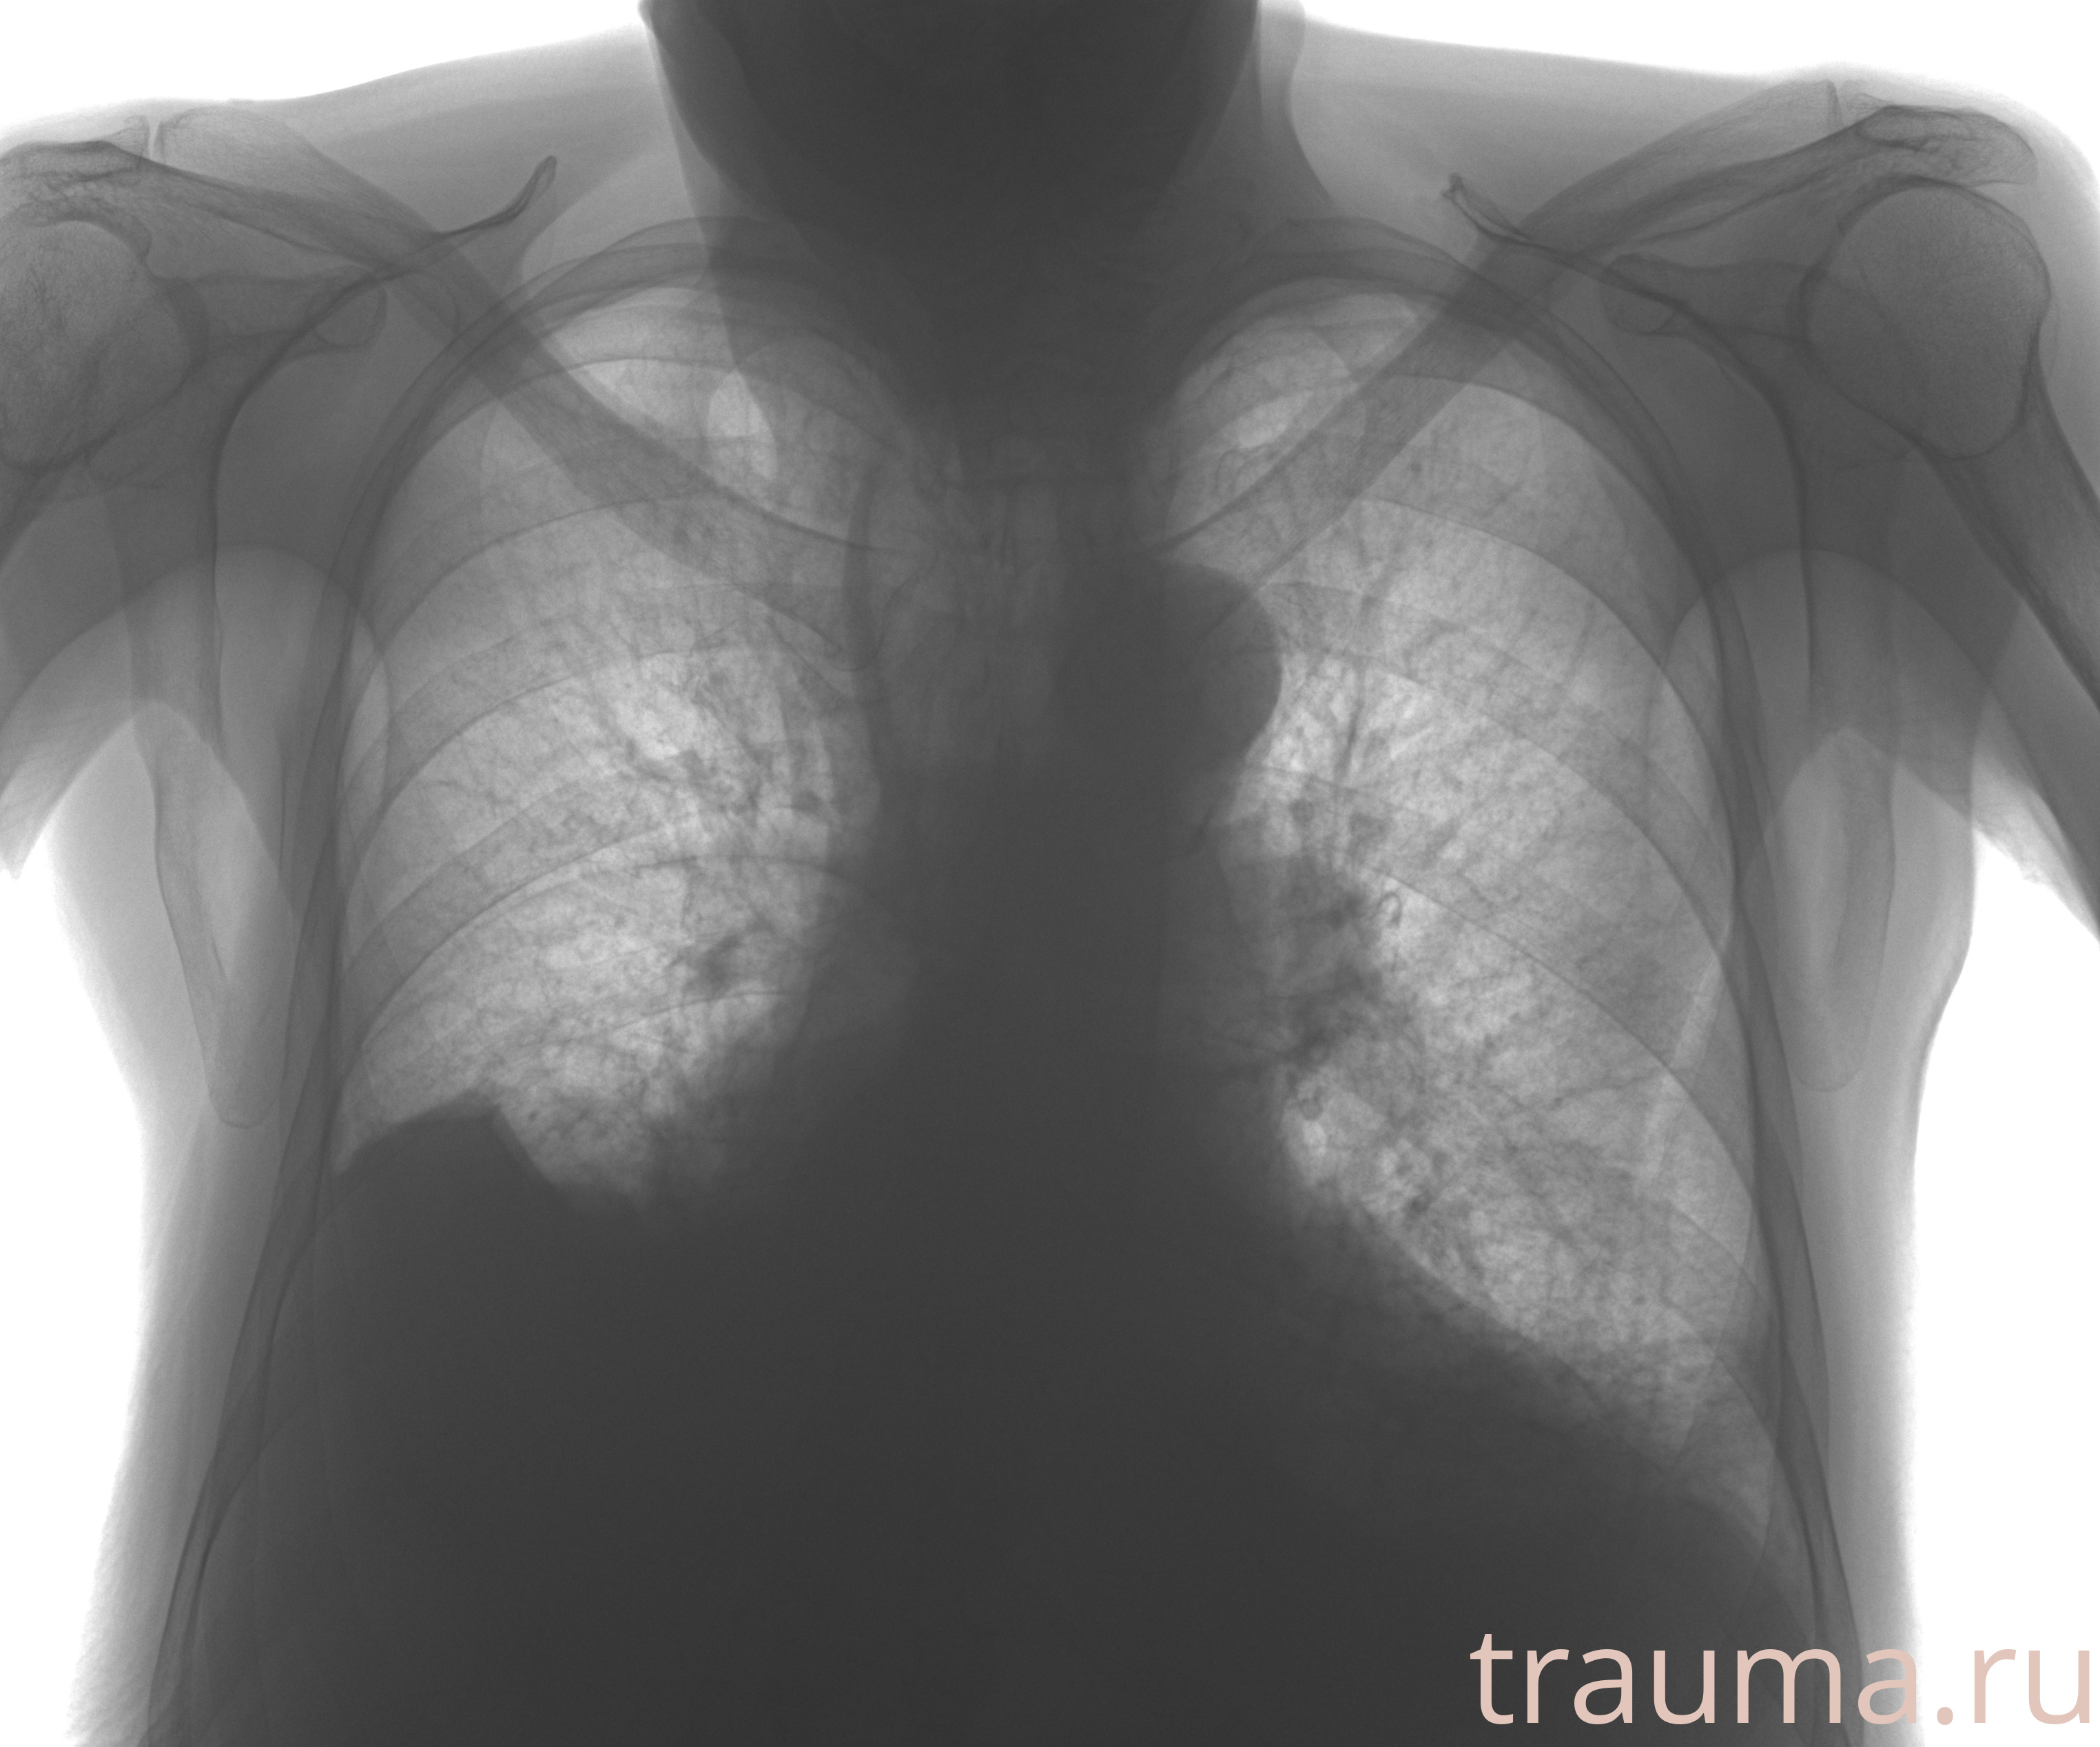

Рентгенограммы

Рентген на дому: по вашему адресу приезжает врач-рентгенолог, травматолог-ортопед с мобильным рентгеновским аппаратом, проводит диагностику травмы или заболевания, делает необходимые рентгенограммы, дает рекомендации по дальнейшему лечению. Получить качественные снимки в домашних условиях возможно благодаря уникальной методике, разработанной МосРентген Центром для института  Склифосовского

Яркость: 1   Контраст: 1   Инвертировать: 0 Увеличение: 1

Перетаскивайте мышь вверх/вниз для контраста, влево/право для яркости. Прокрутка колесом изменяет масштаб. Нажмите Сбросить для возврата к исходному изображению. При увеличении держите мышь в той области, которую хотите рассмотреть.